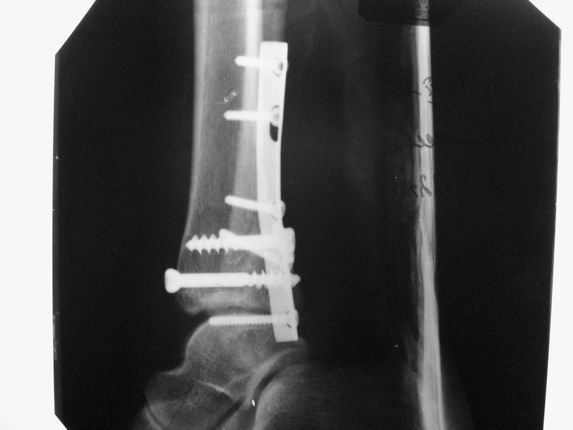

Уважаемые коллеги! Как и обещал, представляю плоды своей работы. Хвалиться особо нечем. Пошли задним

доступом сначала к м/берцовой кости, благодаря смещению линию перелома удалось сразу дифференцировать и по ней узким долотом (без молотка) мобилизовали отломки. Затем выделили задний край, там было проще пройти по линии перелома. Далее пластина по задней поверхности в дистальный отломок, винт проксимальнее пластины и дистрактором с трудом растянули отломки, ощущение было идеальной репозиции м/берцовой кости( доступен осмотр по задней и наружной поверхности), далее винты стандартно. Кстати, положение больной на боку: очень неудобно, но по-другому потом не повернуть на спину, чтобы сделать снимки в стандартных проекциях (ЭОПа нет). Затем дистрактор (два полукольца, спицы), репозиция заднего края, спонгиозный винт с шайбой, слишком проксимально, поэтому + еще один. Доступ к дельтовидной связке: рубец в передней порции, частично иссечен, шов. В общем, длительность операции 3,5 часа, а сказать, что все задуманное получилось, не могу.

А.Минервин.

Отправитель: Djpldas Kuldjanov 16 Март 2006, 17:11

Отличная, грамотная работа, поздравляю, я бы держал в гипсовой повязке до трех недель, затем разработку сустава без нагрузки, нагрузку при такой фиксации,

думаю, можно начать в 6 недель.

Все таки нужно было стянуть ДМС. Судя по снимкам остался подвывих.

Отправитель: Alexander Chelnokov 16 Март 2006, 17:18

Да все прилично получилось, и случай ведь запоздалый, так что все труднее было, чем обычно. Так что присоединяюсь к поздравлениям!